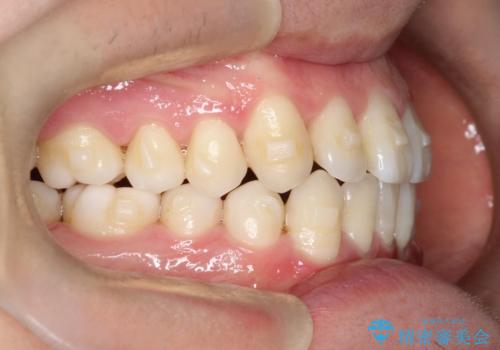

- 前歯のすきっ歯が気になると来院された患者様です。

前歯の隙間をマウスピース矯正(インビザライン)を使用して、閉じていきました。